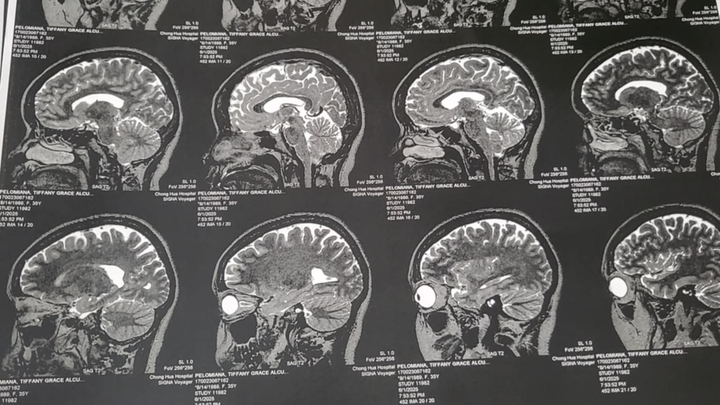

Asking for anything to help my loving sister, who is a single mother of 5. We are in the Philippines, where she can't get the treatment she deserves without the funds upfront for the surgery. She has a bleeding tumor that needs immediate surgery. This is a very difficult time, not being able to get the treatment until the surgery is paid for. Please, anything counts as time is against her.

Thank you all for your kind donations!! Sushi has been in the hospital and continues to receive medical care. The doctors have decided at this time to treat her with medication before choosing to have the brain surgery. All donations will go her hospital stay and her medications. Thank you all for your help and we pray that Sushi will recover soon!